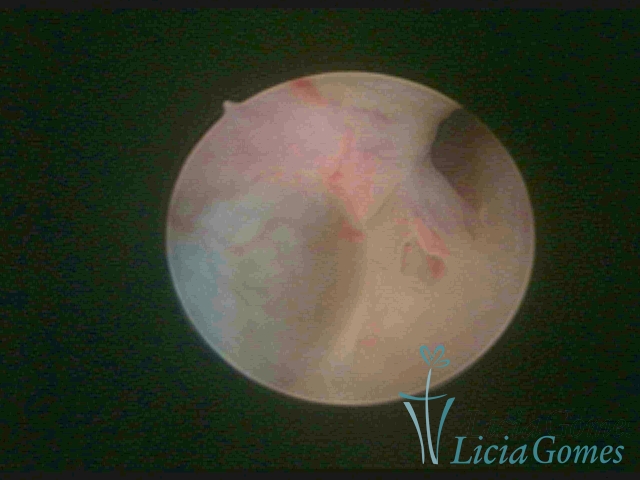

FIBROUS SYNECHIA

Uterine synechiae are scars (adherence) between the surface of the uterine walls, which may occur after the surgical procedure, uterine curettage, or after an inflammatory process in the uterine cavity (endometritis), which may lead to menstrual changes, infertility and obstetric complication such as abortion and premature birth.